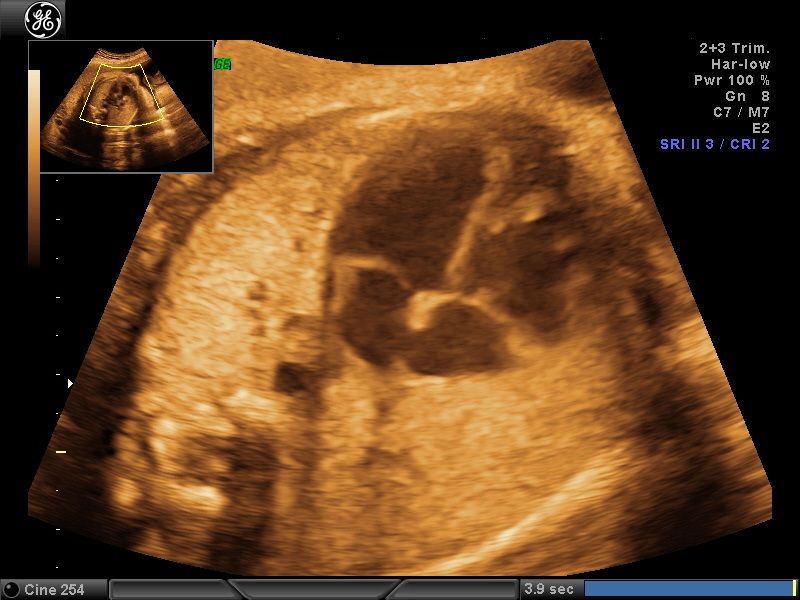

Wykonuję tam około 600 badań „I trymestru ciąży” rocznie, co daje łącznie około 1200 badań z „II trymestrem ciąży” włącznie. Od 15 lat w swoim gabinecie również wykonuję badania prenatalne I, II i III trymestru ciąży w znacznej ilości. To umożliwia mi osiągnięcie doskonałych wyników w diagnostyce tych badań, co stawia mnie w czołówce specjalistów diagnostyki prenatalnej.

Większość swojej kariery zawodowej spędziłem na sali porodowej oraz patologii ciąży. Aktualnie pracuję na sali porodowej. Mam 15-letnie doświadczenie w diagnostyce prenatalnej poparte dużą ilością przebadanych pacjentek i posiadam najszerszy wachlarz certyfikatów z zakresu ultrasonografii płodowej. Corocznie uczestniczę w szkoleniach i kursach ultrasonograficznych.

- diagnostyka prenatalna I,II i III trymestru ciąży z przepływami dopplerowskimi, testem podwójnym (PAPPA i B-HCG), oznaczanie DNA płodowego NIPTY, testy SANCO, NIFTY, VERACITY

• Prowadzenie ciąży, ciąż zagrożonych, nadzór nad ciążą za pomocą USG oraz przepływów dopplerowskich